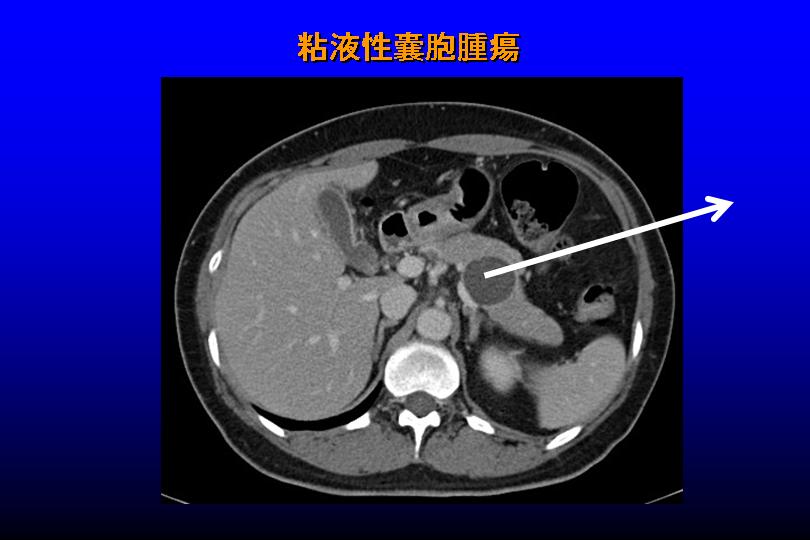

「超音波で切開箇所を固める装置が開発されて、腹腔鏡下手術もやりやすくなった」(田中教授)。膵臓の病変は多くの場合に自覚症状が無く、他のCT検査などで見つかる。A子さんの場合もそうで、膵臓内に大きな粘液性嚢胞腫瘍(写真)を見つけた。放置するとがん化する心配がある。ナスのような形の膵臓は、頭部、体部、尾部という見方をされる。粘液で膨らんだA子さんの腫瘍は、腹腔鏡下で膵臓の半分(体部と尾部)と一緒に切除された。通常なら膵臓の尾部とくっついた脾臓とを一緒に切除するが、田中教授は腹腔鏡下で脾臓部分を残す方法に成功している(参考論文)。

〈写真説明〉いずれもCT画像による。矢印部分(丸く黒い部分)を切除した。